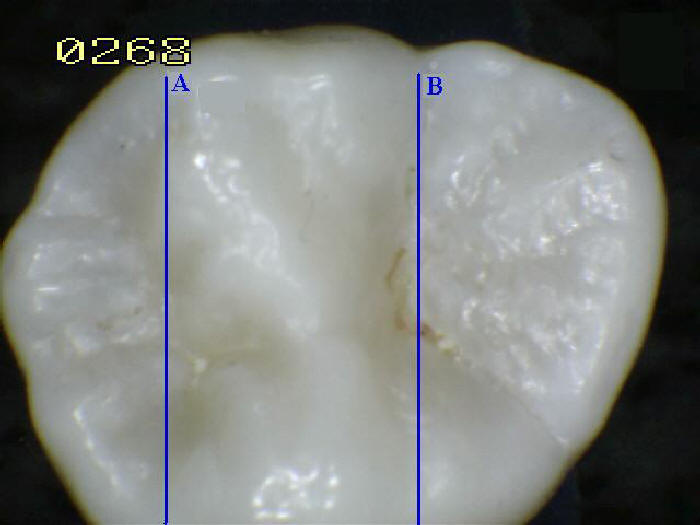

[7] El color normal del esmalte varía de

amarillo claro a blanco grisáceo. En los bordes

de los dientes donde no hay dentina debajo del

esmalte, el color a veces tiene un tono

ligeramente azul. Dado que el esmalte es

semitranslúcido, el color de la dentina y de

cualquier material dental restaurador debajo del

esmalte afecta fuertemente la apariencia de un

diente. El esmalte varía en grosor sobre la

superficie del diente y a menudo es más grueso

en la cúspide, hasta 2.5 mm, y más delgado en su

borde, lo que se ve clínicamente como el CEJ.